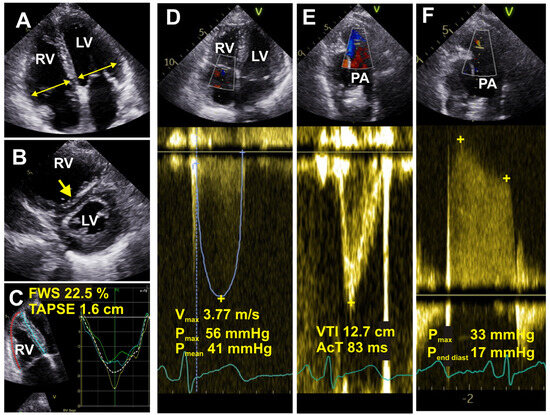

6.5. Echocardiography

- Augustine, D.X.; Coates-Bradshaw, L.D.; Willis, J.; Harkness, A.; Ring, L.; Grapsa, J.; Coghlan, G.; Kaye, N.; Oxborough, D.; Robinson, S.; et al. Echocardiographic assessment of pulmonary hypertension: A guideline protocol from the British Society of Echocardiography. Echo Res. Pract. 2018, 5, G11–G24. [Google Scholar] [CrossRef]

- Nowak, J.; Hudzik, B.; Jastrzȩbski, D.; Niedziela, J.T.; Rozentryt, P.; Wojarski, J.; Ochman, M.; Karolak, W.; Żegleń, S.; Gierlotka, M.; et al. Pulmonary hypertension in advanced lung diseases: Echocardiography as an important part of patient evaluation for lung transplantation. Clin. Respir. J. 2018, 12, 930–938. [Google Scholar] [CrossRef]

- Mandoli, G.E.; De Carli, G.; Pastore, M.C.; Cameli, P.; Contorni, F.; D’Alessandro, M.; Bargagli, E.; Mondillo, S.; Cameli, M. Right cardiac involvement in lung diseases: A multimodality approach from diagnosis to prognostication. J. Intern. Med. 2021, 289, 440–449. [Google Scholar] [CrossRef] [PubMed]

- Arcasoy, S.M.; Christie, J.D.; Ferrari, V.A.; Sutton, M.S.J.; Zisman, D.A.; Blumenthal, N.P.; Pochettino, A.; Kotloff, R.M. Echocardiographic Assessment of Pulmonary Hypertension in Patients with Advanced Lung Disease. Am. J. Respir. Crit. Care Med. 2003, 167, 735–740. [Google Scholar] [CrossRef] [PubMed]

- Cowie, B.; Kluger, R.; Rex, S.; Missant, C. The utility of transoesophageal echocardiography for estimating right ventricular systolic pressure. Anaesthesia 2015, 70, 258–263. [Google Scholar] [CrossRef] [PubMed]

- Ni, J.-R.; Yan, P.-J.; Liu, S.-D.; Hu, Y.; Yang, K.-H.; Song, B.; Lei, J.-Q. Diagnostic accuracy of transthoracic echocardiography for pulmonary hypertension: A systematic review and meta-analysis. BMJ Open 2019, 9, e033084. [Google Scholar] [CrossRef] [PubMed]